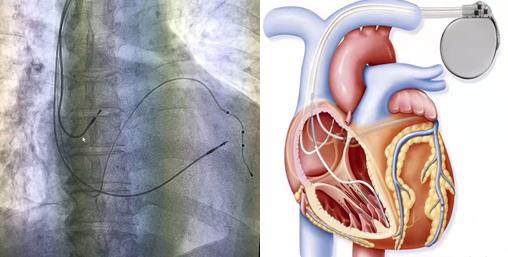

手術過程:手術開始,患者在局部麻醉下,順利穿刺左側腋靜脈成功后,依次植入右室主動電極、過鞘管送遞長鞘、沿長鞘送十極至冠狀動脈竇口,推送進冠狀竇遠端,沿十極電極遞送長鞘至冠狀竇,取出十極電極,在雙導絲支撐下送造影球囊進行造影,選擇合適的心左側靜脈后,順利植入左室電極,再植入右房主動電極,多體位投照各電極位置合適、測試起搏參數均符合要求,遂固定電極后植入起搏器。歷經2.5小時, 三腔起搏器植入術順利完成,患者各項參數檢測均正常。

目前常用的“單(雙)腔心臟起搏器”均只能治療心動過緩,但三腔起搏器可實現心臟再同步化治療(CRT)目的,不但具有治療心動過緩的功能,還能解決由于患者左右心室收縮不同步而導致的心衰癥狀。它是在傳統的雙腔起搏(右心房,右心室起博)的基礎上增加了左心室起搏,左室起搏電極經右房的冠狀靜脈竇開口,進入冠狀靜脈左室后側壁支起搏左室,通過多部位起搏恢復左右心室同步收縮,增加左心室充盈時間,減少室間隔矛盾運動,減少二尖瓣返流,從而改善患者的心臟功能,甚至可以讓擴大的心臟回縮,提高運動耐量以及生活質量。